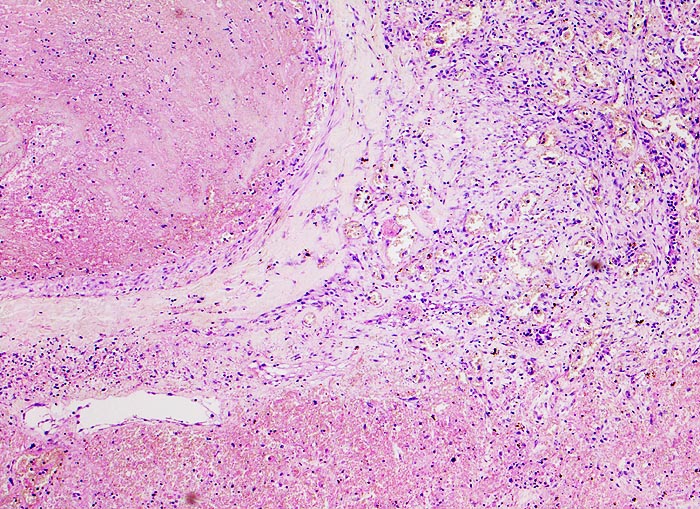

hämorrhagischer Lungeninfarkt bei Lungenembolie

Links im Bild ein Pulmonalarterienast mit einem frischen Embolus. Das Lungenparenchym rechts im Bild ist nekrotisch und stark hämorrhagisch.

Tiefe Beinvenenthrombosen bei metastasierendem Prostatakarzinom. Koronare Herzkrankheit.